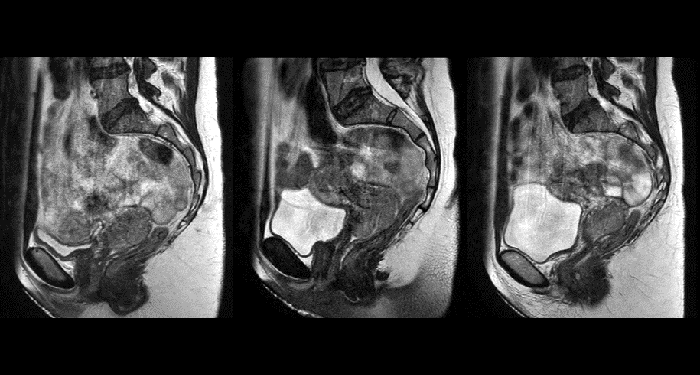

Unlike CT, MRI images are created without using ionizing radiation. This is particularly important when the patients are children, in which exposure to a radiation dose should be minimized to reduce long-term secondary effects. The option to acquire multiple MRI exams paves the road towards “plan-of-the-day” approaches or monitoring treatment response for adaptive strategies.

Arhus University Hospital at the forefront of MRI guidance in adaptive cervical cancer radiotherapy.